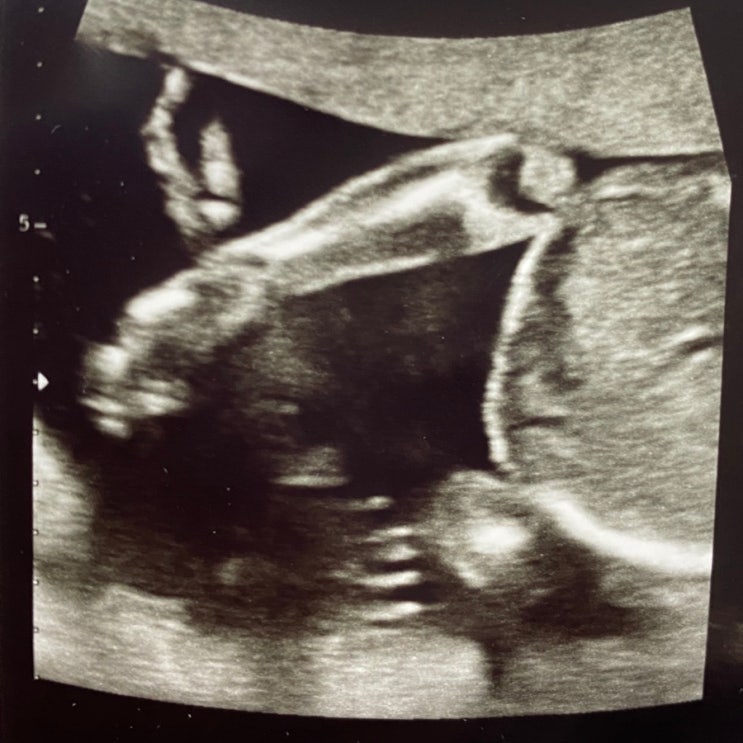

??10월 예적금 두둑히(정밀초음파) /신혼일기??

??10월 예적금 두둑히(정밀초음파) /신혼일기?? ??정밀초음파 보고왔어요?? 벌써 ...

??♀️임신 중기 초음파(+독감주사) /신혼일상??♀️

??♀️임신 중기 초음파(+독감주사) /신혼일상??♀️ 없어졌는줄 알았던 입덧이 다시 시작.......